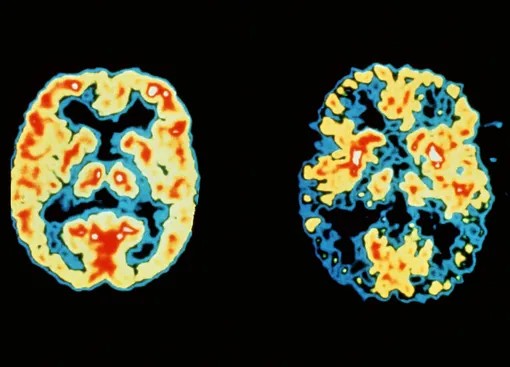

До сих пор ученые не нашли никакого способа полностью вылечить болезнь Альцгеймера, но с каждым годом становятся все ближе к пониманию механизмов развития заболевания и разработке эффективных методов лечения.